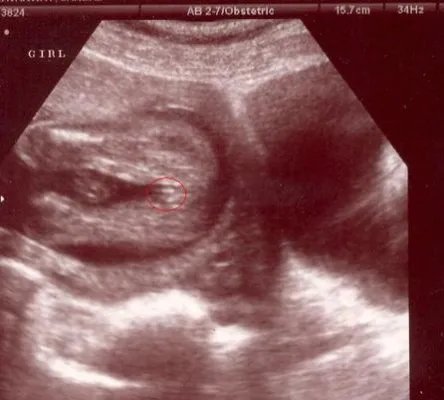

首先是女宝宝的, “三线” 是一个明显的标记: